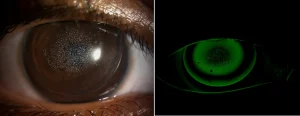

| Behind the veil, a glimpse of elegance and grace — where every dimple tells a story of timeless beauty | Dimple veiling is a phenomenon that occurs on the cornea, where small indentations or “dimples” appear on the eye’s surface. This is often caused by rigid contact lenses that do not fit perfectly against the cornea. These dimples create a veiling or hazy effect, causing blurry vision or slight distortion. The gaps between the lens and the cornea diffuse light, leading to this visual disturbance. Dimple veiling can be observed during a slit-lamp examination by an eye care professional and may indicate an imperfect lens fit or a change in the shape of the cornea. |